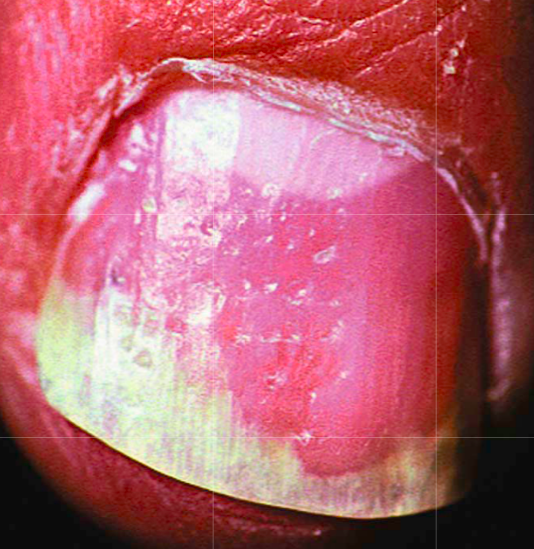

Diagnosis

oil spot of psoriasis

nail pitting and distal onycholysis

Psoriasis